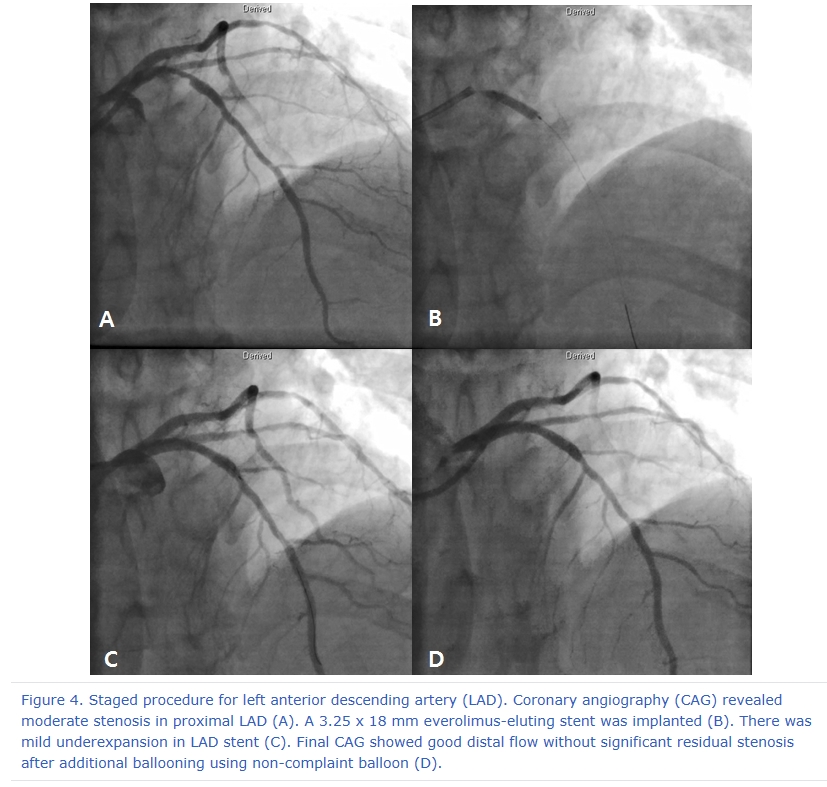

After 3 days later, we performed 2nd stage PCI for proximal LAD. CAG reveled moderate stenosis in proximal LAD (Figure 4A), so we examined optical coherence tomography (OCT) for further evaluation. It showed large amount of plaque (minimal lumen area [MLA] 2.62 mm2) (Figure 5A and 5C). We directly implanted 3.25 and 18 mm everolimus-eluting stent (Xience Alpine®), but follow-up CAG showed mild under-expansion, so we did additional ballooning using 3.25 x 10mm non-complaint balloon (Figure 4B and 4C). Follow-up OCT and CAG showed good distal flow without significant residual stenosis. (post-PCI cross sectional area [CSA] 6.65 mm2) (Figure 4D, 5B and 5D). Because of no-reflow phenomenon for RCA in previous PCI, we performed follow-up CAG and OCT for RCA. CAG and OCT showed stent underexpansion with neointima rupture and large amount of residual thrombi in mid RCA (MLA 2.39 mm2) (Figure 6A, 6B, 7A and 7C). So we did ballooning using 3.25 x 10 mm non-complaint balloon for mid RCA (Figure 6C). Follow-up CAG and OCT showed good distal flow without significant residual stenosis. (CSA 5.03 mm2) (Figure 6D, 7B and 7D). He was discharged without any complications.

Figure 4. Staged procedure for left anterior descending artery (LAD). Coronary angiography (CAG) revealed moderate stenosis in proximal LAD (A). A 3.25 x 18 mm everolimus-eluting stent was implanted (B). There was mild underexpansion in LAD stent (C). Final CAG showed good distal flow without significant residual stenosis after additional ballooning using non-complaint balloon (D).